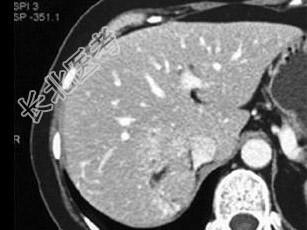

- 单项选择题中年患者,女性, 偶然发现肝团块,结合图像, 最可能的诊断是 ( )

A、肝癌

B、肝血管平滑肌脂肪瘤

C、局灶性结节增生

D、肝腺瘤

E、转移癌